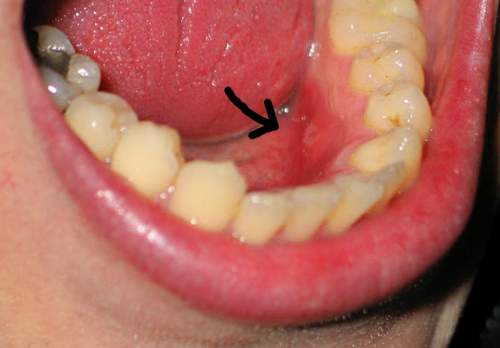

Một vết loét áp-tơ ở mặt trong lợi..

Tổn thương loét áp-tơ có nhiều dạng, có thể xuất hiện ở bất cứ vị trí nào trong miệng, nhưng không thấy ở mặt trên lưỡi, môi và vòm khẩu cứng. Những vết loét áp-tơ nhẹ có hình tròn với đường kính nhỏ hơn 10mm. Hầu hết vết loét có đường kính từ 2-3mm, trung tâm màu trắng. Các vết loét này thường gây đau và tự biến mất sau 3 - 14 ngày, không để lại sẹo. Những vết loét áp-tơ nặng thường tổn thương sâu hơn và có đường kính trên 1cm trở lên.